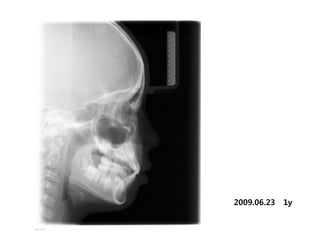

1998.09.25/M

C.C

• Max. protrusion

Dx

• Mentalis action, incorrect tongue posture

Goal

• Establish perioral muscle tone and tongue

posture

2009.06.23   1y